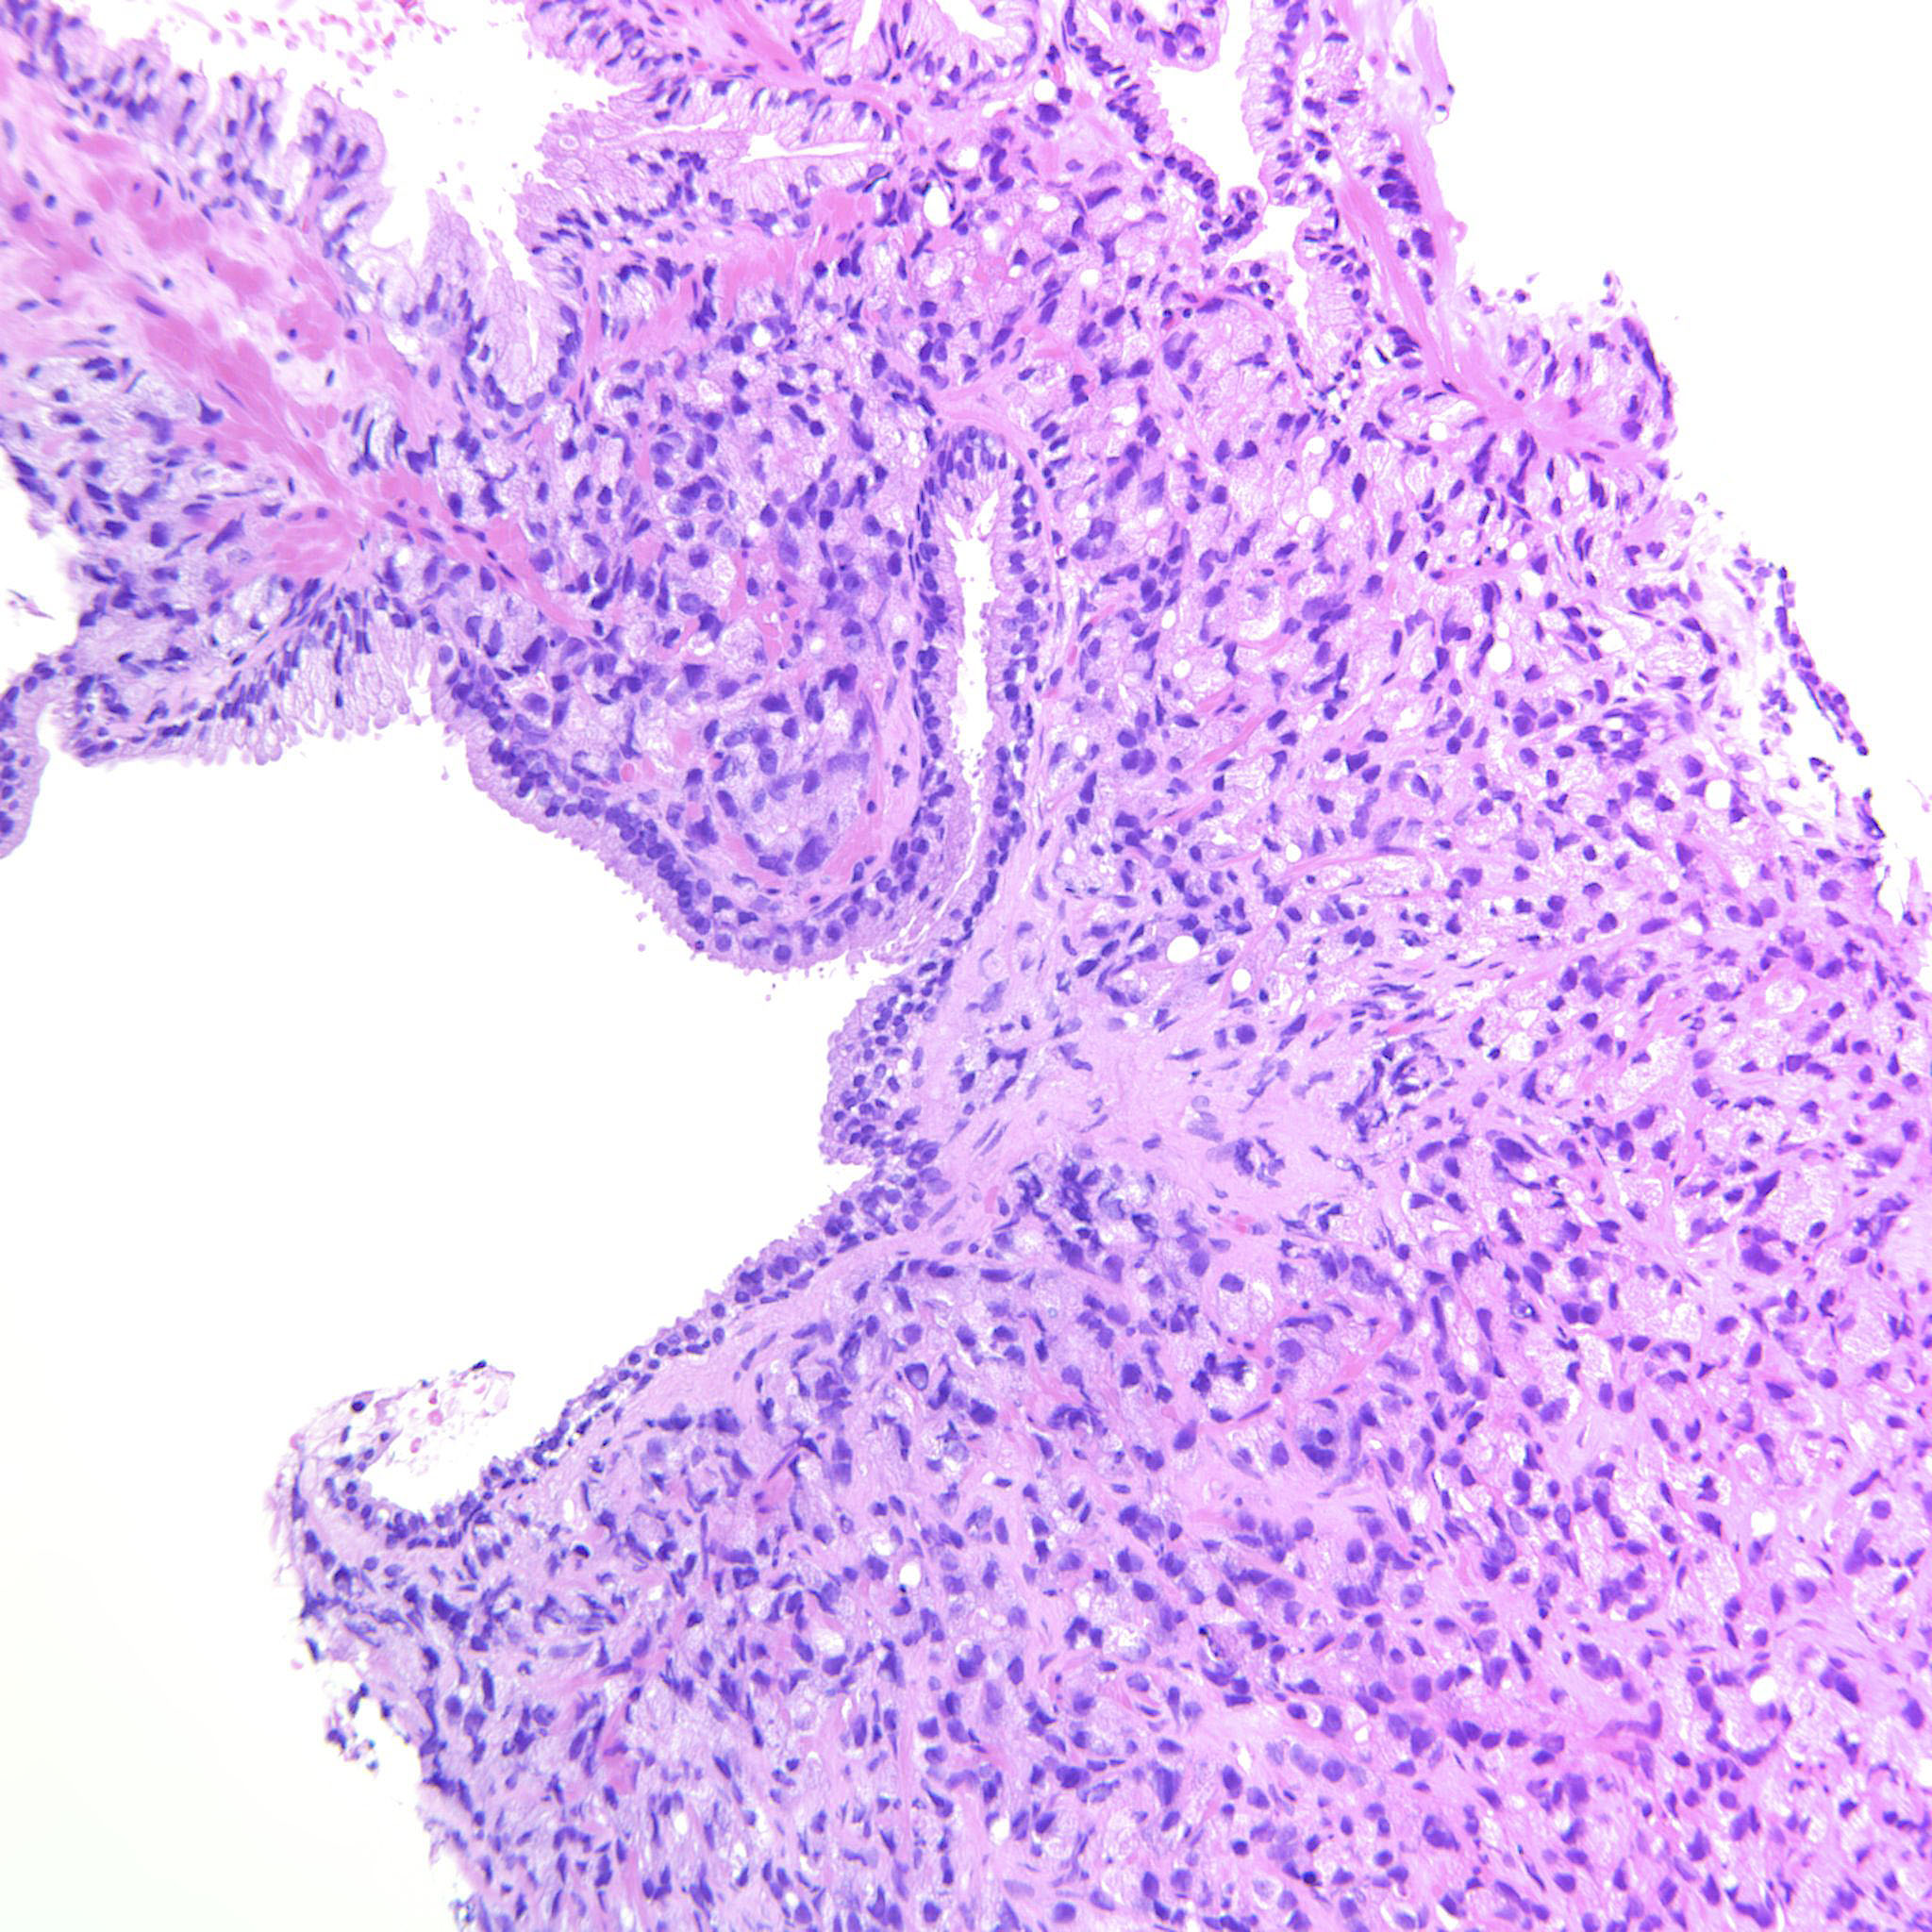

Consensus grade: GS 9-10 (ISUP 5)

GS 4+5=9 (90% pattern 4). Also some low volume grade 3 in last image. |

Case description (by case creator):

Large sheets of fused glands but also sheets of tightly packed pale single cells.